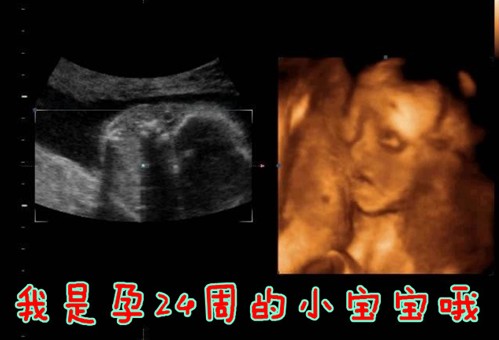

杭州玛莉亚妇产医院四维彩超专家介绍:四维彩超是利用超声波原理成像的,能够对胎儿进行动态、立体彩超检查,显示胎儿的四肢、面、各器官的发育情况,甚至胎儿在母体里的状态也可以观察到;对胎儿畸形,如唇 裂、腭裂、骨骼发育异常、心血管畸形等能早期诊断,大大提高胎儿畸形的检出率及准确率,减少出生缺陷儿的发生。

一般来说,四维彩超单胎的蕞佳检查时间是在怀孕的23-27周,双胎则为22-23周。因为这个时期的胎宝宝结构已经形成,宝宝的大小及羊水适中,在宫内的活动空间较大,胎儿骨骼回声影响比较小,检查的图像也就比较清晰。如果检查时间太早,则不能达到蕞好的检查效果。

四维彩超能清楚直观地显示胎儿面部情况及其相互关系,尤其是能够动态、多角度地观察宫内胎儿的颜面部、肢体的发育情况,甚至可以动态地观察到胎儿在母体里的状态,看到宝宝打哈欠、揉眼睛等可爱的动作。